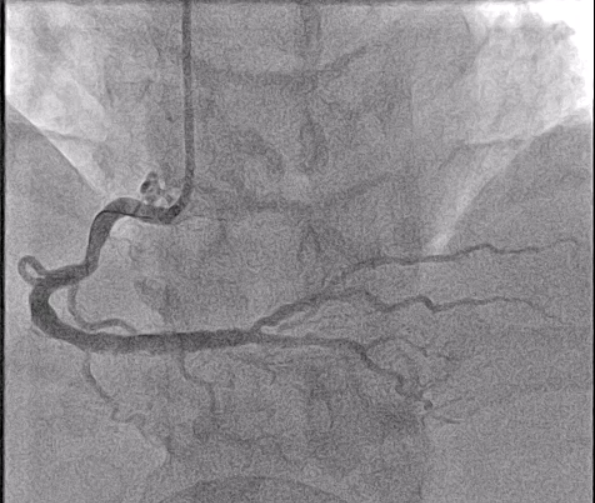

ECG showed normal sinus rhythm with ST elevation in II, III and AvF. Complete blood count, electrolytes and kidney function were within normal limits. Troponin-t was not available before catheterization. Coronary angiogram through a right radial approach showed single vessel disease with a diffuse critical stenosis at the distal RCA bifurcation (Medina 1,1,0) with a severe size mismatch between the distal RCA and RPDA.

PCI was performed with a 7Fr JR4 Guide with wires in the RPDA and RPL. Lesion was predilated and stented with a 2.75x33m DES and postdilated with a 4.5mm NC proximal to the RCA bifurcation. IVUS showed underexpansion distally and severe malapposition proximally hence the stent was further postdilated with 2.75mm NC distally and 4.5mm in the distal RCA. ClearStent showed unravelling of the stent, which was confirmed on IVUS with a new total stent length of 52mm. The distal RCA diameter had grown in size to 5mm at the site of the proximal stent edge. A 4.5x24mm DES was implanted in the distal RCA to cover the unravelled stent struts, which was postdilated with a 5mm NC balloon. Final IVUS showed the stent to have adequate apposition with no immediate complications.

Case Summary